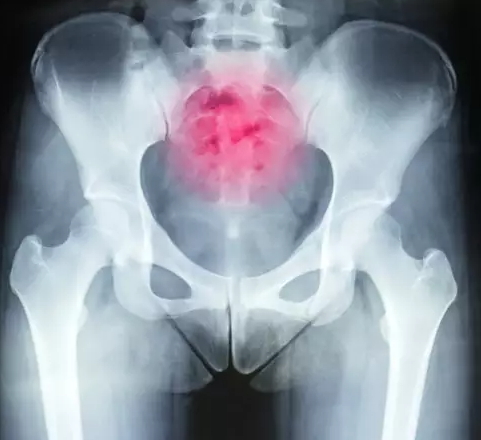

꼬리뼈가 당장 충격을 받지 않았어도 과거 엉덩이 등의 부상은 꼬리뼈를 구부리고 엉치뼈 주변의 신경을 자극해 통증을 유발할 수 있습니다.

글또 허리디스크가 아닌데 엉치뼈 주변이 통증이 있다면 좌골점액낭염을 의심할 수 있는데요. 이경우는 의자에서 장시간 근무하는 직장인이나 수험생들에게 주로 발생합니다.

앉을때 엉치뼈가 아파서 대장항문외과와 척추전문의의 정밀 검사가 필요할 때가 있는데요. 이 경우는 항문거근 증후군이라고 직장과 항문 주변 사이에 근육이 뭉쳐서 배변을 보다가도 꼬리뼈에 자극이 가면서 생기면서 엉치뼈 통증으로 나타나면 이때는 정밀검사를 해보셔야 합니다.

특히 겨울철 빙판길에서 넘어지면 엉덩방아를 찧어 외상으로 꼬리뼈 인대가 손상되고 엉치뼈에 통증이 발생되는데요. 특히 나이 드신 분분들이 조심하셔야 됩니다.